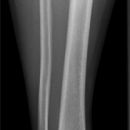

Unterschenkel a.-p. (1. Ebene)

Orthograde Darstellung des Kniegelenkspalts, Patella mittelständig. Distaler Unterschenkel mit Darstellung des Sprunggelenkspaltes.